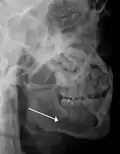

Plain film radiography

Traditionally, plain films of the mandible would be exposed but had lower sensitivity and specificity owing to overlap of structures. Views included AP (for parasymphsis), lateral oblique (body, ramus, angle, coronoid process) and Towne's (condyle) views. Condylar fractures can be especially difficult to identify, depending on the direction of condylar displacement or dislocation so multiple views of it are usually examined with two views at perpendicular angles.[11]

lateral oblique image demonstrating a fractured mandible.